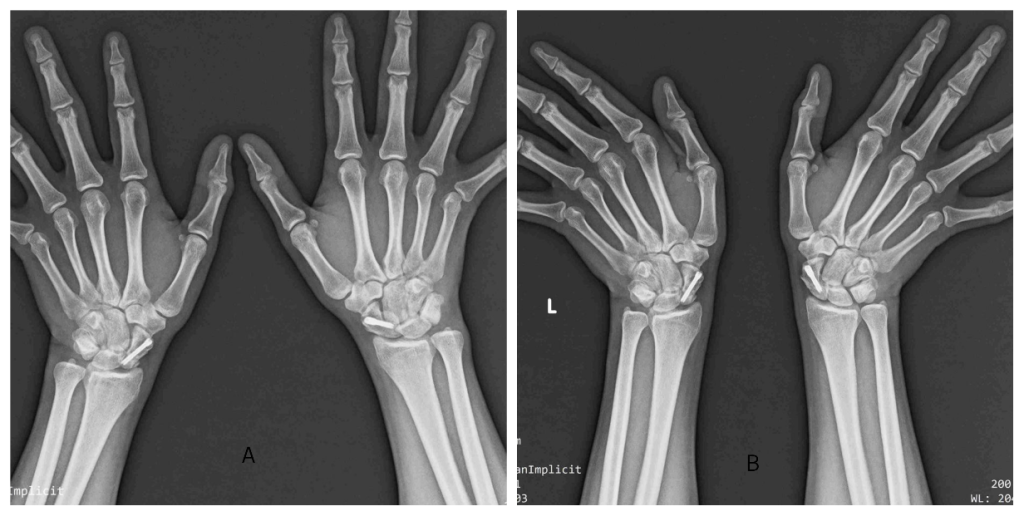

On examination, there was tenderness in the anatomical snuff box on both sides, and the scaphoid compression test was positive bilaterally. There was a significant restriction in the movements of both wrists. He was evaluated with X-rays (Fig. 1) and CT (Fig. 2) of the bilateral wrist and was diagnosed as a case of bilateral closed scaphoid fracture (Herbert type B4 on the left side and type B2 on the right side) with transcaphoid, trans-triquetrum perilunate dislocation on the left side and coronoid fracture (Regan-Moorey II) on the left side (Fig. 3). Closed reduction of perilunate dislocation was done in an emergency under local anesthesia, and a bilateral glass holding slab was applied for scaphoid fracture. While the patient had no prior comorbidities, bone health markers such as serum calcium and Vitamin D levels were evaluated and found to be within the normal range. The patient had no history of smoking or alcohol consumption. These may be important determinants of healing, particularly in older or systemically compromised individuals.

Figure 1: Pre-operative X-rays of the bilateral wrist. Anteroposterior (a) and lateral (b) view of the left wrist. Anteroposterior (c) and lateral (d) view of the right wrist.